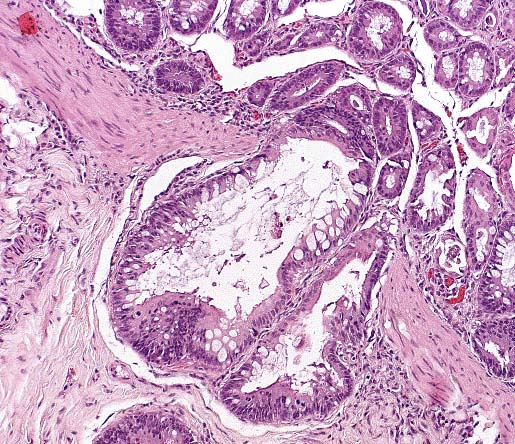

Crypt herniation in a measles-infected tamarin. (HE, 100X, 106K)

A measles epidemic has been reported in a marmoset colony, with high morbidity and mortality. Clinical signs included edema of the upper eyelids, progressive lethargy, nasal discharge, focal erythema and edema, and maculopapular rash. Histologically, there was interstitial pneumonia with giant cells and intranuclear inclusions. Giant cells were also found in lymph nodes, spleen, and gut-associated lymphoid tissue (GALT) of the colon. In another reported outbreak of measles in tamarins, Saguinus mystax, rash was not observed. Measles infections in New World monkeys can also the characterized, as in this case, by gastrointestinal disease, with epithelial necrosis. Syncytial giant cells form in mucosal epithelium, lamina propria, and GALT.

This case illustrates that measles infection in New World primates may present differently than in macaques. Clinically, this tamarin had severe diarrhea, with no detected rash. Histologically, the infection was apparently confined to the intestinal tract; syncytia were not found in other organs (lymph nodes, spleen, liver, urinary bladder, lung). During this outbreak, one other adult tamarin died, with similar histologic and immunohistochemical findings; a third animal died of other causes, but manifested mild intestinal involvement with few syncytial cells in the mucosal epithelium.

AFIP Diagnosis: Colon: Colitis, necrotizing, subacute, diffuse, moderate, with crypt herniation, lymphoid depletion, syncytial cells, and intranuclear and intracytoplasmic inclusion bodies, tamarin, primate.